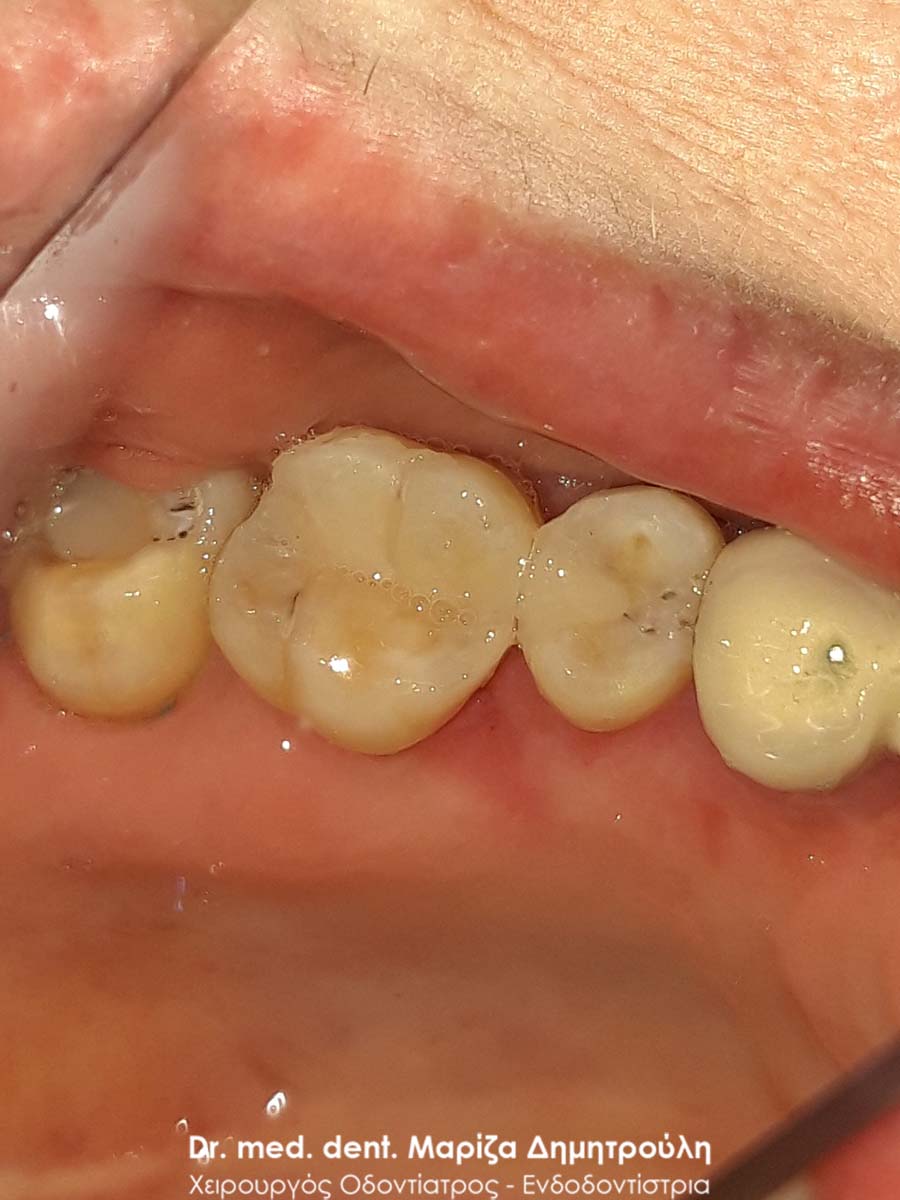

Περιστατικό – Λευκά σφραγίσματα δύο δοντιών

Στο παρόν περιστατικό απουσιάζει η αρχική εικόνα των δύο δοντιών πριν αρχίσει ο εκτροχισμός τους. Διαθέσιμες είναι μόνο η ενδιάμεση εικόνα που παρουσιάζει το εύρος του οδοντικού ελλείμματος στα δύο γομφίους της αριστερής πλευράς της άνω γνάθου και η τελική εικόνα αποκατάστασης των δύο δοντιών.

Η ασθενής αισθανόταν τις τελευταίες μέρες έναν ήπιο πόνο κατά τη μάσηση τροφών. Μετά την κλινική εξέταση του στόματος διαπιστώθηκε η ύπαρξη τερηδονικών κοιλοτήτων στους δύο άνω αριστερούς γομφίους. Αποφασίστηκε με τη συναίνεση της ασθενούς η αντικατάσταση των σφραγισμάτων. Στον πρώτο γομφίο διορθώθηκε μόνο η μισή έκταση του παλιού σφραγίσματος, καθώς κρίθηκε οτι δεν ήταν απαραίτητη η αφαίρεση ολόκληρου του παλιού σφραγίσματος.

ΠΡΙΝ

META